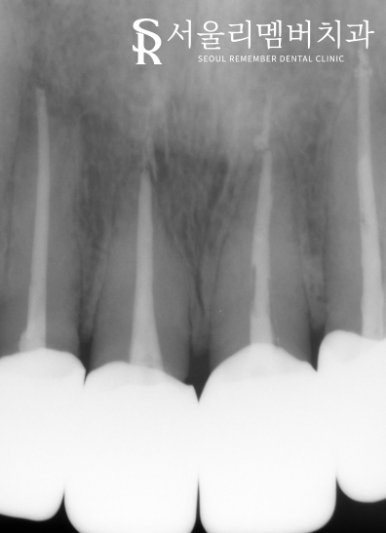

서울대입구역치과 에서는 앞서 계획했던 대로

전치부 엔도를 진행했습니다.

감염된 곳을 깨끗하게 제거한 뒤에

소독을 진행했는데요.

이후 충전재를 사용하여

비어있는 근관을 꼼꼼하게 채워 넣었습니다.

잔존 치질의 양이 모자란 것과

확실한 밀폐를 돕기 위한 코어 작업까지 마쳤다면